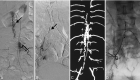

Background and purpose: Spinal arteriovenous shunts below the conus constitute 3 types of lesions, which have previously been mainly described in case reports, given their rarity, and are sometimes misdiagnosed. The purpose of this study was to describe the features of each type and compare these types as to epidemiologic features, clinical and radiologic presentations, treatment, and outcomes in a consecutive series of 48 cases.

Materials and methods: The prospectively collected data bases of 2 referral centers for spinal vascular lesions were retrospectively reviewed. Spinal arteriovenous shunts below the conus were defined as all dural and intradural shunts below the conus medullaris. Clinical features, radiologic findings, treatment results, and clinical outcomes were assessed.

Results: There were filum terminale arteriovenous fistulas in 11 patients (22.9%), radicular arteriovenous shunts in 7 patients (14.6%), and spinal dural arteriovenous fistulas in 30 patients (62.5%). Radicular arteriovenous shunts presented at a younger age (P = .017) and with a higher incidence of back pain symptoms (P = .037). A tethered spinal cord was found in 54.5% of patients with filum terminale arteriovenous fistulas and 23.3% of patients with spinal dural arteriovenous fistulas. After treatment, the angiographic complete obliteration rate was 89.4% and spinal function was improved significantly (P < .001).

Conclusions: Three groups of spinal arteriovenous shunts below the conus can be differentiated according to clinical and radiologic features. Filum terminale arteriovenous fistulas are frequently associated with dysraphic malformations, which may suggest a particular embryologic origin.